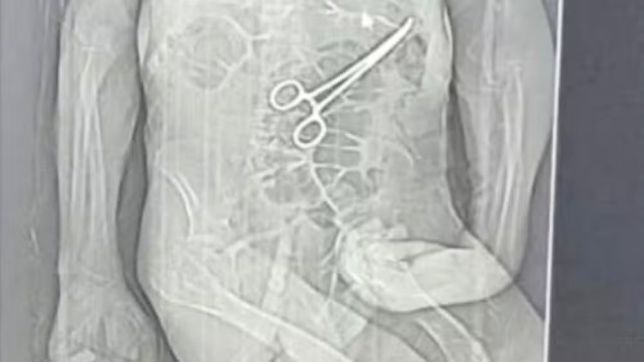

A família de Manoel Cardoso de Brito, de 68 anos, acusa o Hospital Municipal de João Pinheiro, no Noroeste de Minas, de erro médico após o idoso morrer na véspera do Natal. Segundo os parentes, uma pinça cirúrgica foi esquecida dentro do corpo do paciente após a primeira cirurgia, fato que, segundo os familiares, só veio à tona depois do óbito.

A Secretaria Municipal de Saúde João Pinheiro confirmou, em nota, que houve a retirada de um corpo estranho durante a cirurgia do paciente e alegou que Manoel estava em estado grave, com várias comorbidades. Informou ainda que reforçou protocolos de segurança e abriu sindicância para apurar o caso. Leia mais abaixo.

Foto: Reprodução

Segundo o advogado da família do idoso, Iuri Evangelista Furtado, as medidas legais começaram a ser adotadas depois que um exame de tomografia, divulgado por uma rádio local, chegou ao conhecimento de parentes. A imagem indicaria a presença do instrumento cirúrgico no corpo do paciente.